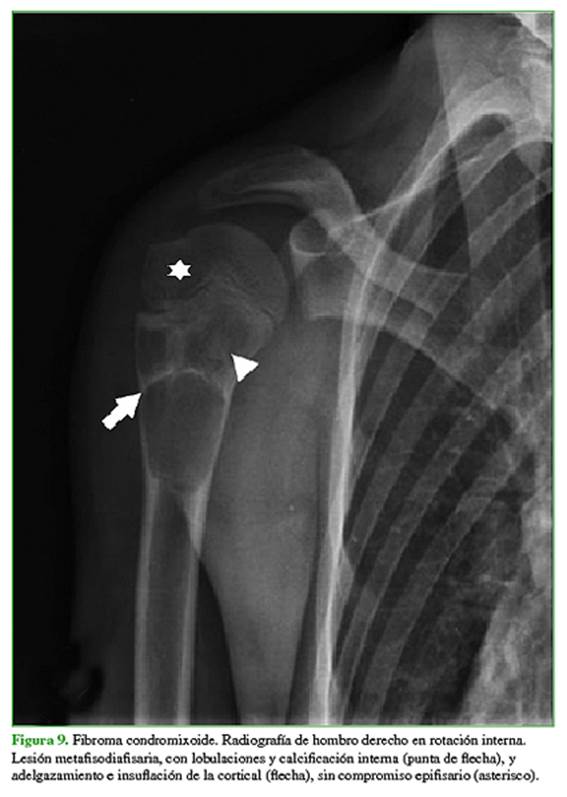

Los diagnósticos diferenciales más frecuentes son focos de hiperplasia de médula ósea grasa, displasia fibrosa (Figura 5), quiste óseo simple o aneurismático (Figura 6), lesiones condrales (encondroma, condrosarcoma) (Figura 7), infarto óseo antiguo, necrosis avascular (Figura 8) y fibroma condromixoide (Figura 9).